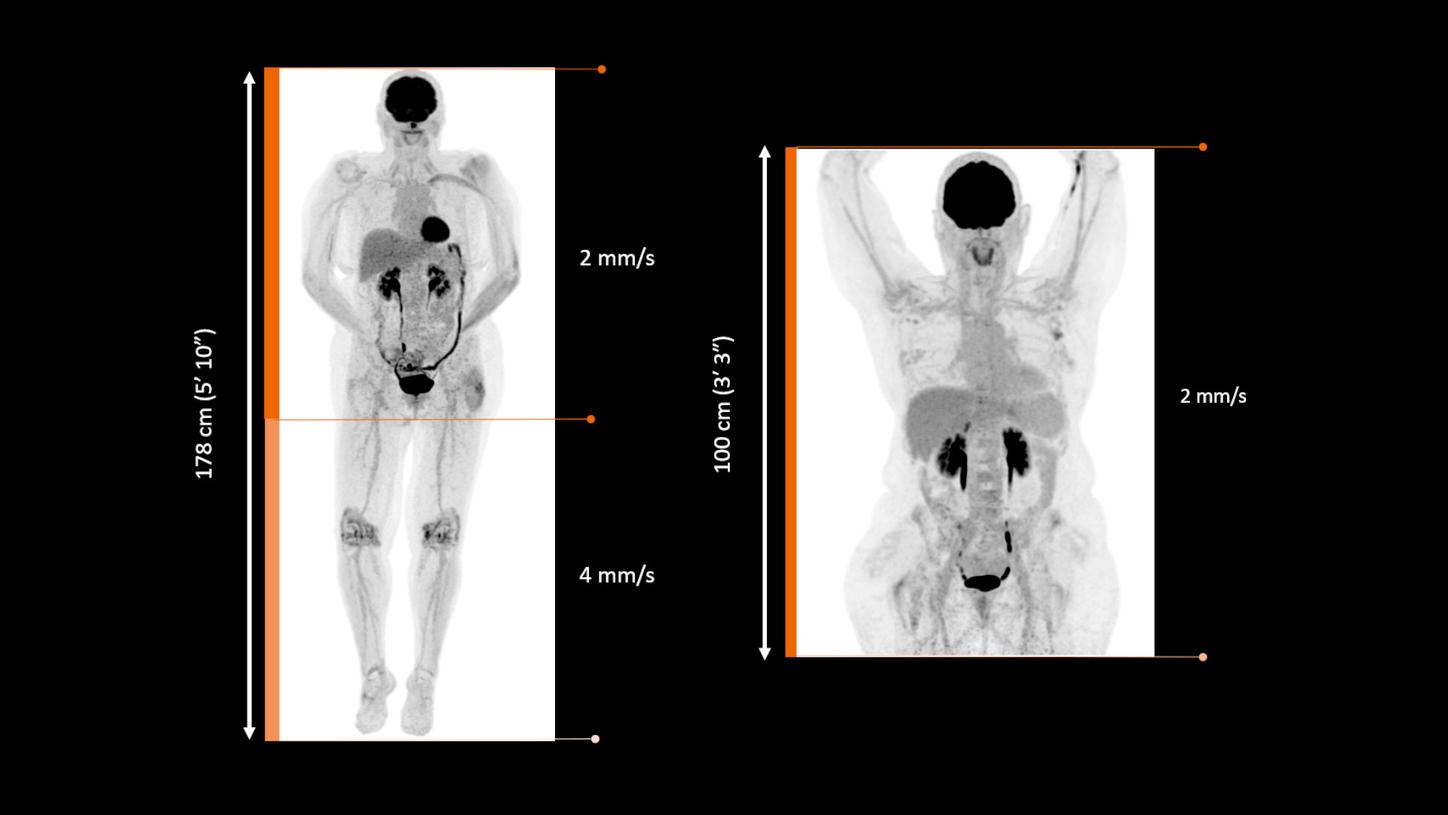

Boundless imaging

Maximize effective aFOV by eliminating bed overlap.